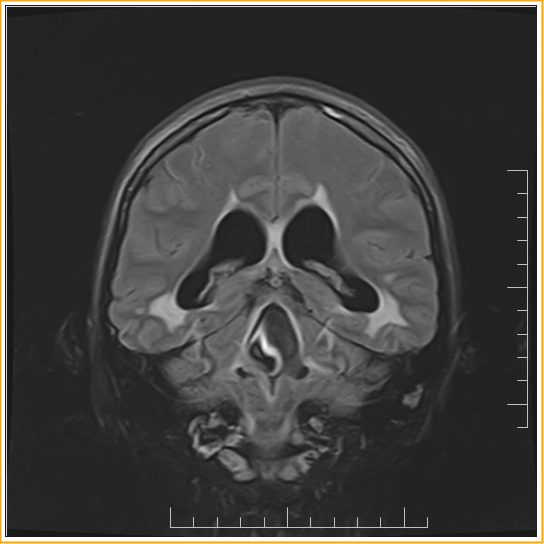

Obstruction of Magendie's Foramen :MRI

A 33-year-old woman presented with visual disturbance and balance difficulty on MRI brain shows dilatation of lateral, III and IV ventricles along with periventricular T2/FLAIR hyperintensity. Temporal horns are dilated. Fourth ventricle appears dilated out of propotion along with prominent CSF flow void in the IV ventricle and some enhancement in ependymal surface of IV ventricle. Contour abnormality in the foramen of magendie. These findings are indicative of IV ventricular outflow tract obstruction possibly post infective sequele/arachnoiditis in foramen of magendie